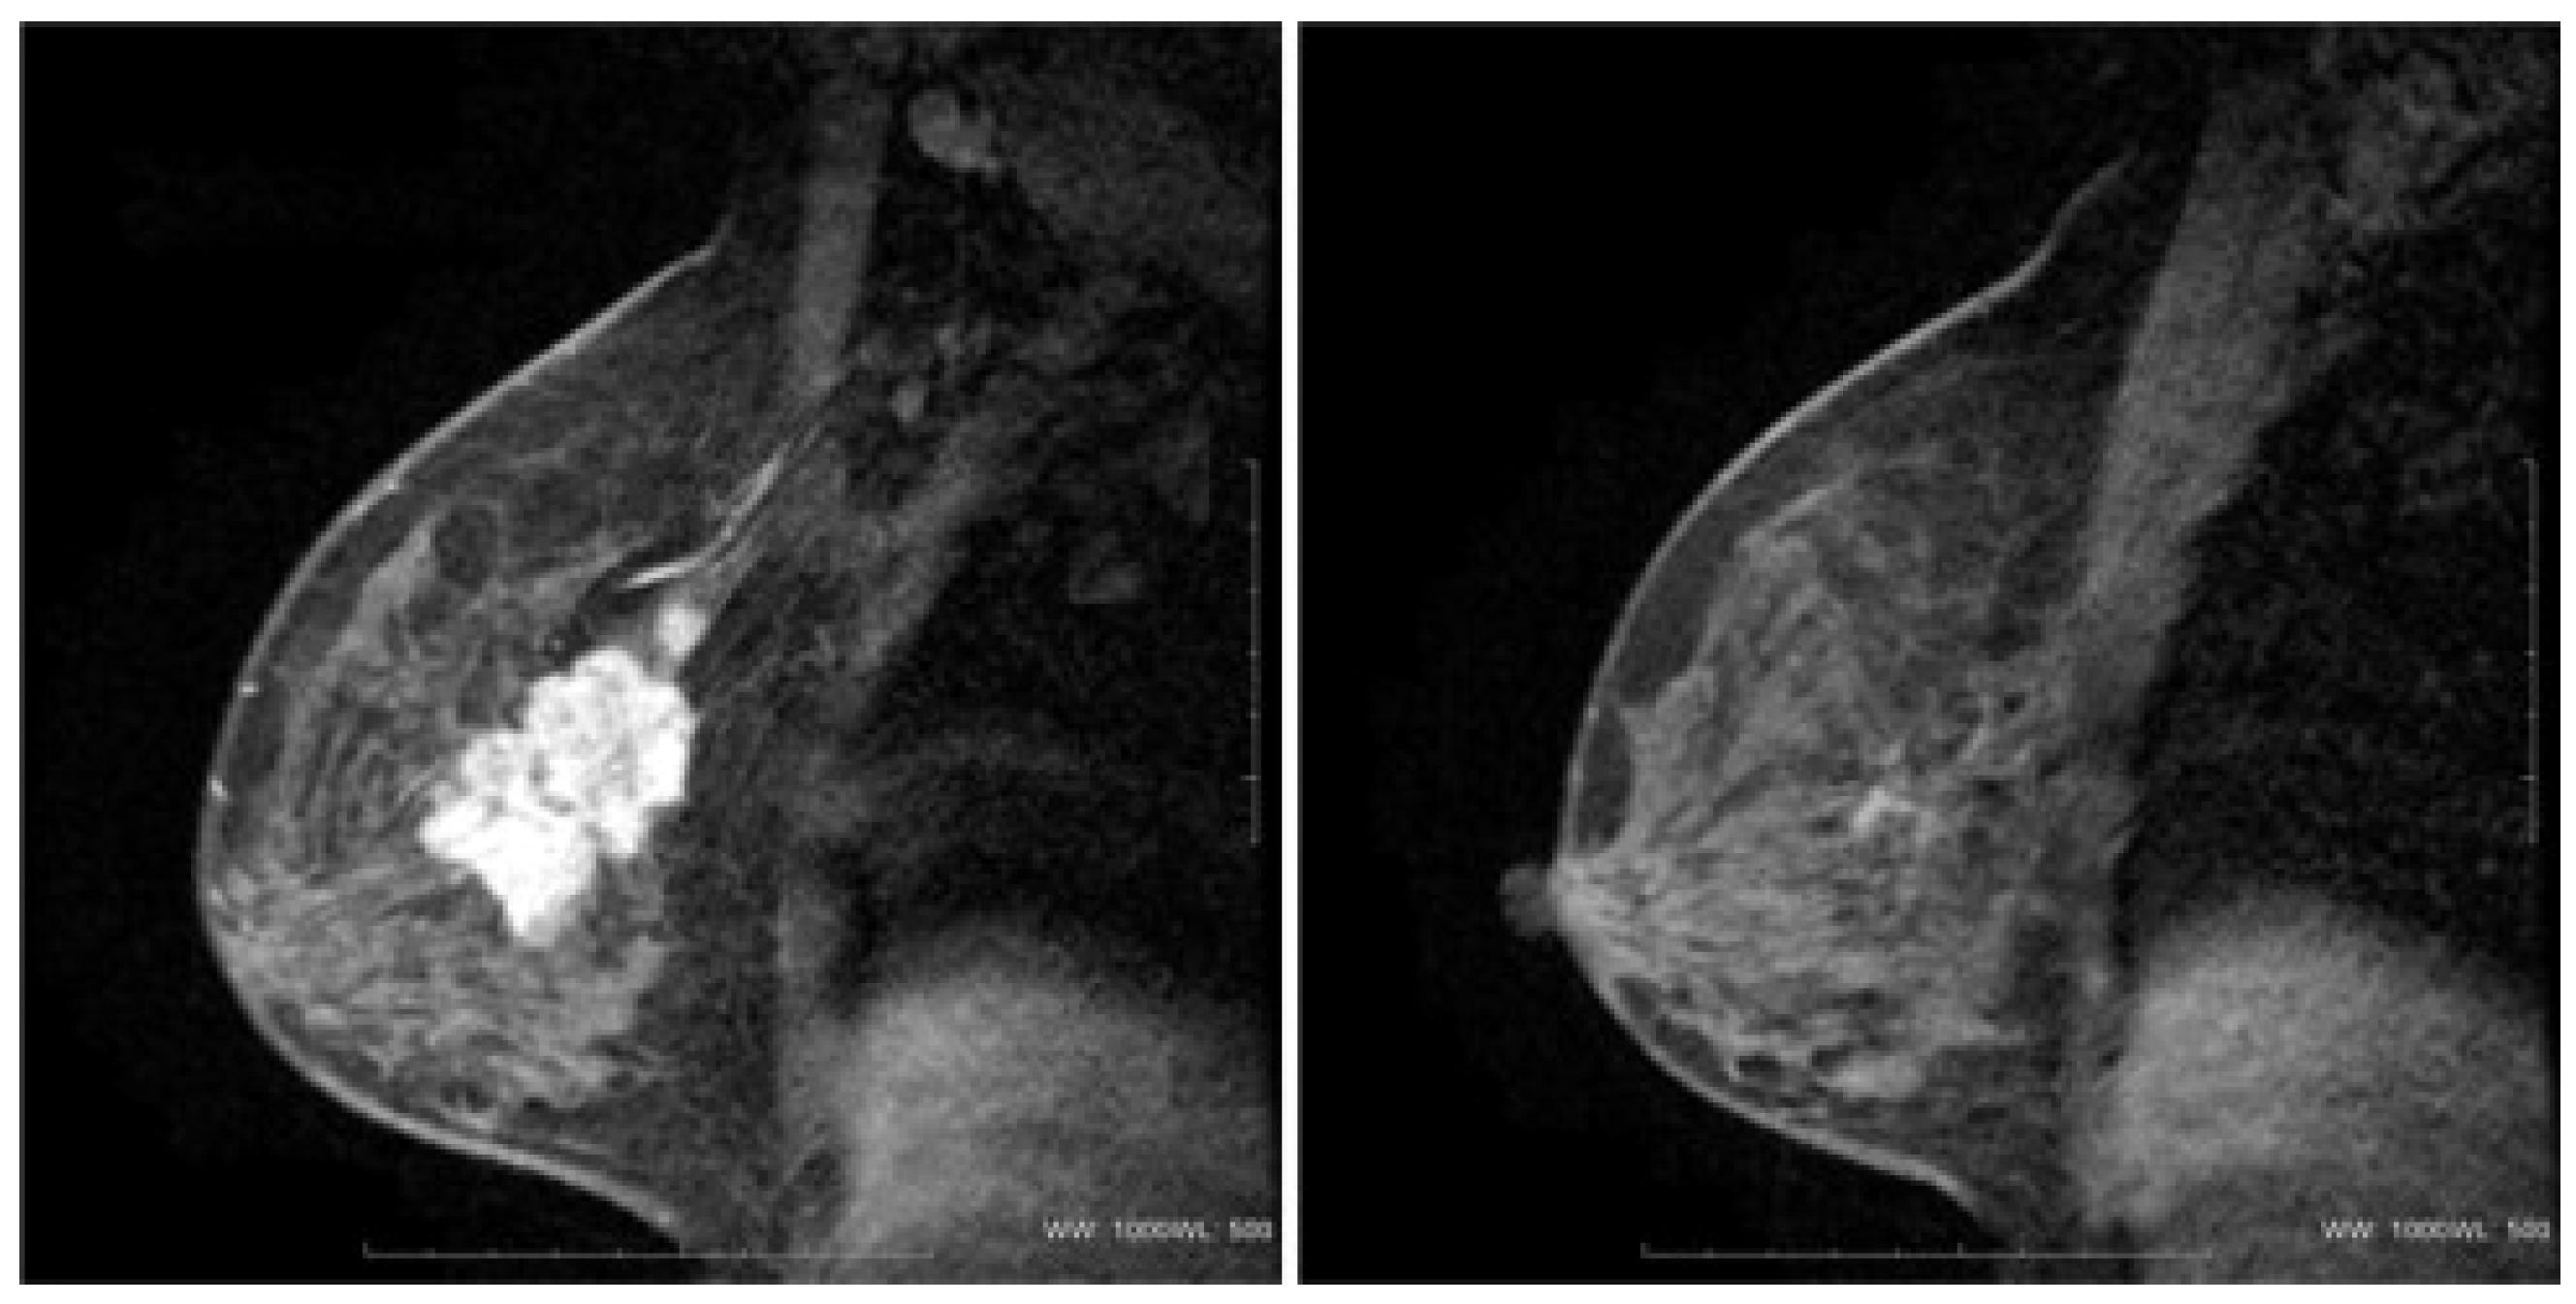

2.1. MRI

- Li, Y.L.; Zhang, X.P.; Li, J.; Cao, K.; Cui, Y.; Li, X.T.; Sun, Y.S. MRI in diagnosis of pathological complete response in breast cancer patients after neoadjuvant chemotherapy. Eur. J. Radiol. 2015, 84, 242–249. [Google Scholar] [CrossRef]